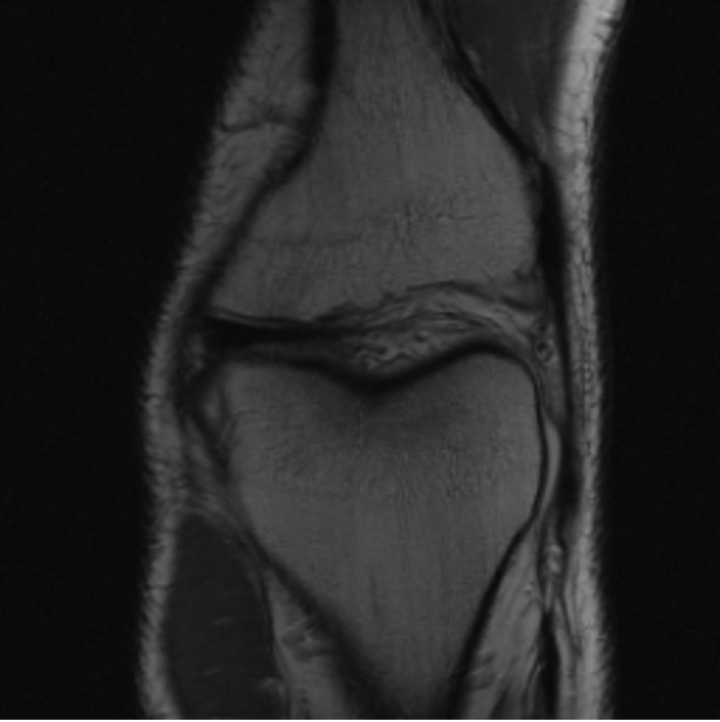

5.3 Out-of-Domain Generalisation

One way to test the generalization capability of the trained X-Diffusion is to test it on a completely different domain from an MRI dataset not seen during training. We report the single-slice results on NYU fastMRI [37, 82], a knee MRI dataset, using the X-Diffusion trained on the BRATS brain MRIs. The results are shown in Figure 9 and Table 2. It shows how successfully X-Diffusion is able to generate knee MRIs from a single image, despite not seeing knees at all in training. To qualitatively assess how realistic our generated 3D volumes were (produced from a single slice), we gave 20 generated examples alongside their real MRI counterparts to an expert orthopaedic surgeon. He was then asked to identify the real example from a given pair. The surgeon identified with certainty only 10 real knee MRIs out of 17, while could not decide on the remaining 3 of the 20 MRI pairs. This further validates the generated out-of-domain MRIs.

The Effect of Pretraining. We hypothesize that the massive pretraining of our X-Diffusion based on Stable Diffusion weights [57] played an important role. Another aspect is that the Zero-123 [41] weights which are modified Stable Diffusion weights that understand viewpoints and fine tuned on large 3D CAD dataset Objaverse [20] can indeed be the reason why X-Diffusion generalizes well to out-of-domain dataset (see generalization to knee MRIs in Figure XI).